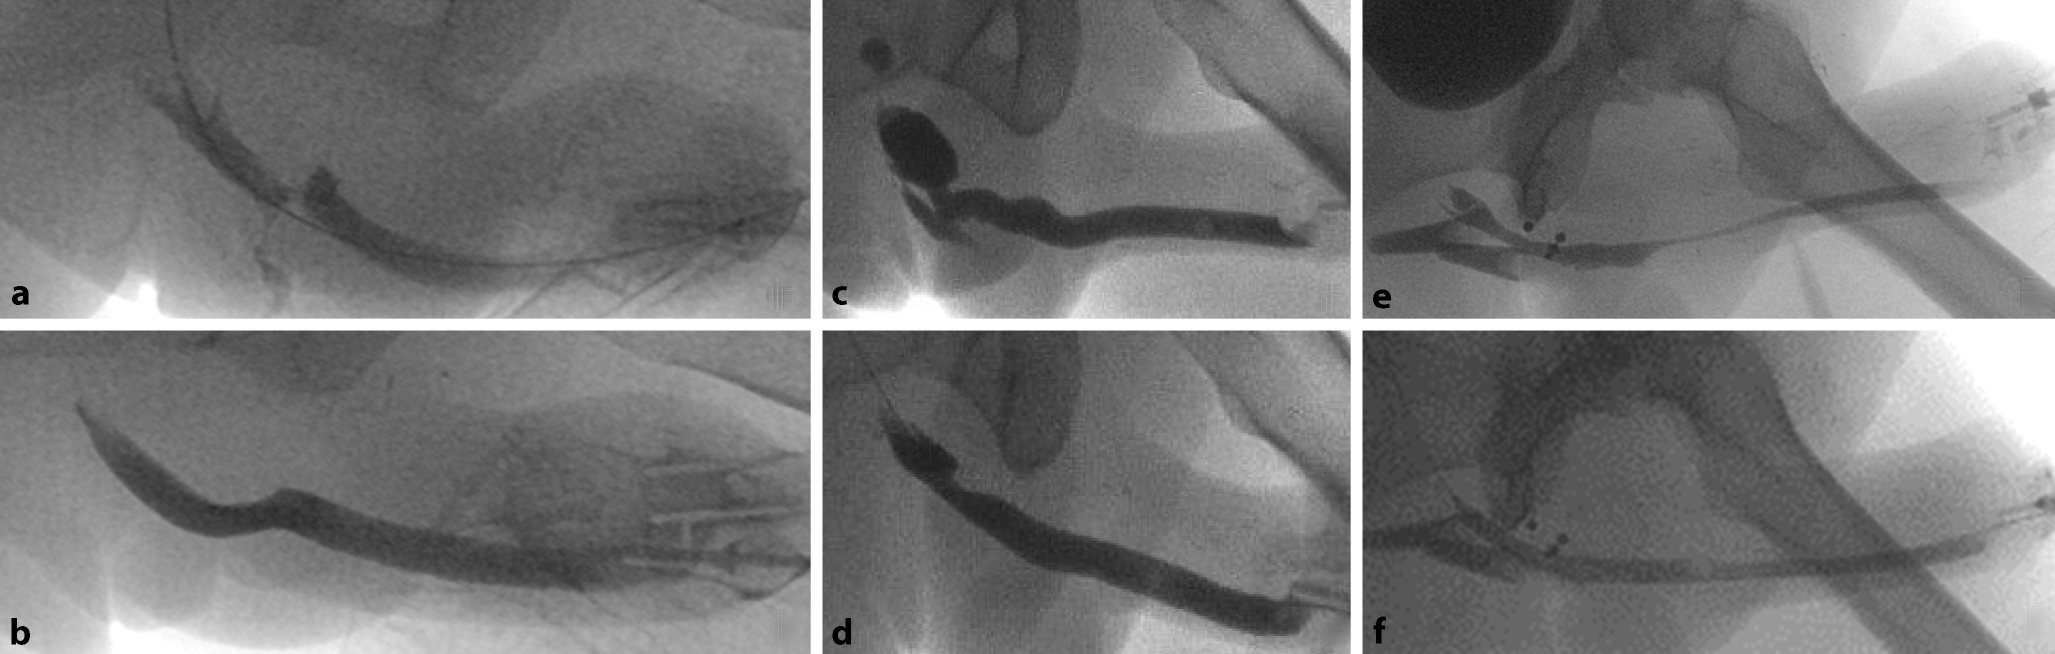

Handelt es sich um rezidivierende langstreckige Strikturen, sollte ein zweizeitiges Vorgehen bevorzugt werden. Wie in Abb. 7 dargestellt, wird in einem ersten Schritt die strikturierte Urethra komplett eröffnet und zur Schaffung einer breiteren Urethraplatte ein ausreichend grosser Graft um die strikturierte eröffnete Urethra eingenäht. Als Graft können Mundschleimhaut oder Haut (Vollhaut, Meshgraft) verwendet werden. Nach komplettem Einheilen nach 3–6 Monaten erfolgt die Retubularisierung der Urethra mit Verschluss des Penoids. Hierbei werden Offenheitsraten bis 70 % erreicht [11]. Zur Behandlung der Meatusstenosen wird die Meatusplastik empfohlen.

Abb. 7

a Retrogrades Urethrogramm präoperativ mit Nachweis einer Striktur und schliesslich vollständigem Abbruch sowie b antegrades und retrogrades Urethrogramm präoperativ mit Darstellung der Urethra bis in den Anastomosenbereich Pars fixa/Pars pendulans mit distaler Striktur hiervon; c retrogrades Urethrogramm postoperativ nach d offener zweizeitiger Urethraplastik mit Meshgraft vom Oberschenkel und sekundärer Tubularisierung. (Mit freundl. Genehmigung, ©Feicke, Universitätsspital Basel, alle Rechte vorbehalten)

Bild vergrößern